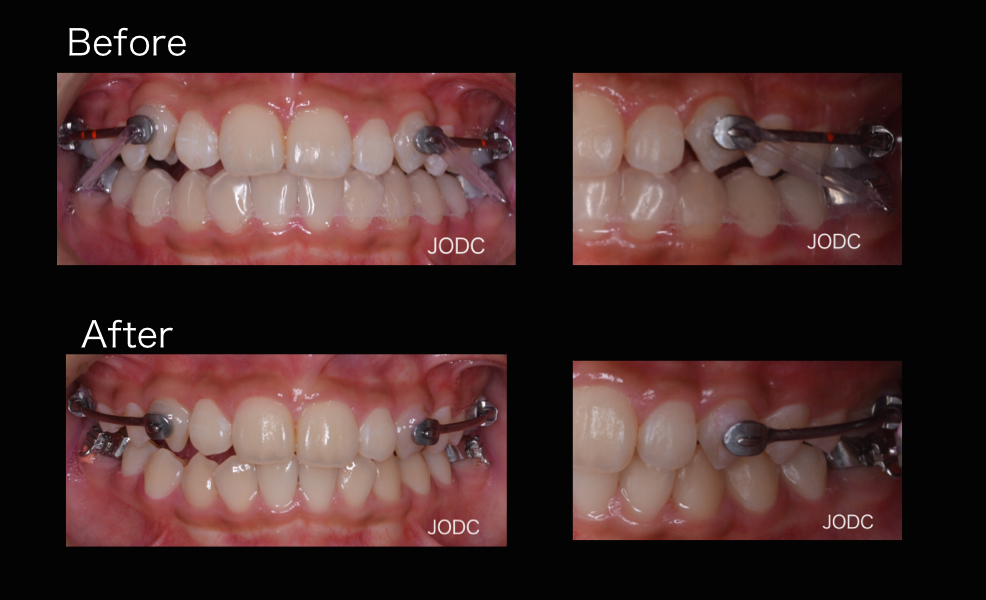

【2】カリエール

上顎前突「出っ歯」の改善を目的とする装置で、上顎左右犬歯から大臼歯を遠心移動する為に使用します。

“カリエール”を口腔内に装着し、下顎左右第一大臼歯の装置とカリエールに顎間ゴムをかけます。

顎間ゴムをかけることで上顎は後方へ、下顎は前方へ誘導される力がかかります。この作用で上下顎の顎関係の改善をはかります(After写真は約1ヶ月後)。

犬歯から第一大臼歯にかけて遠心移動し、上下顎がしっかり咬み合う所まで誘導できました。カリエールを装着する事で後の矯正治療で行うブラケット装置での治療期間を短縮することができます。